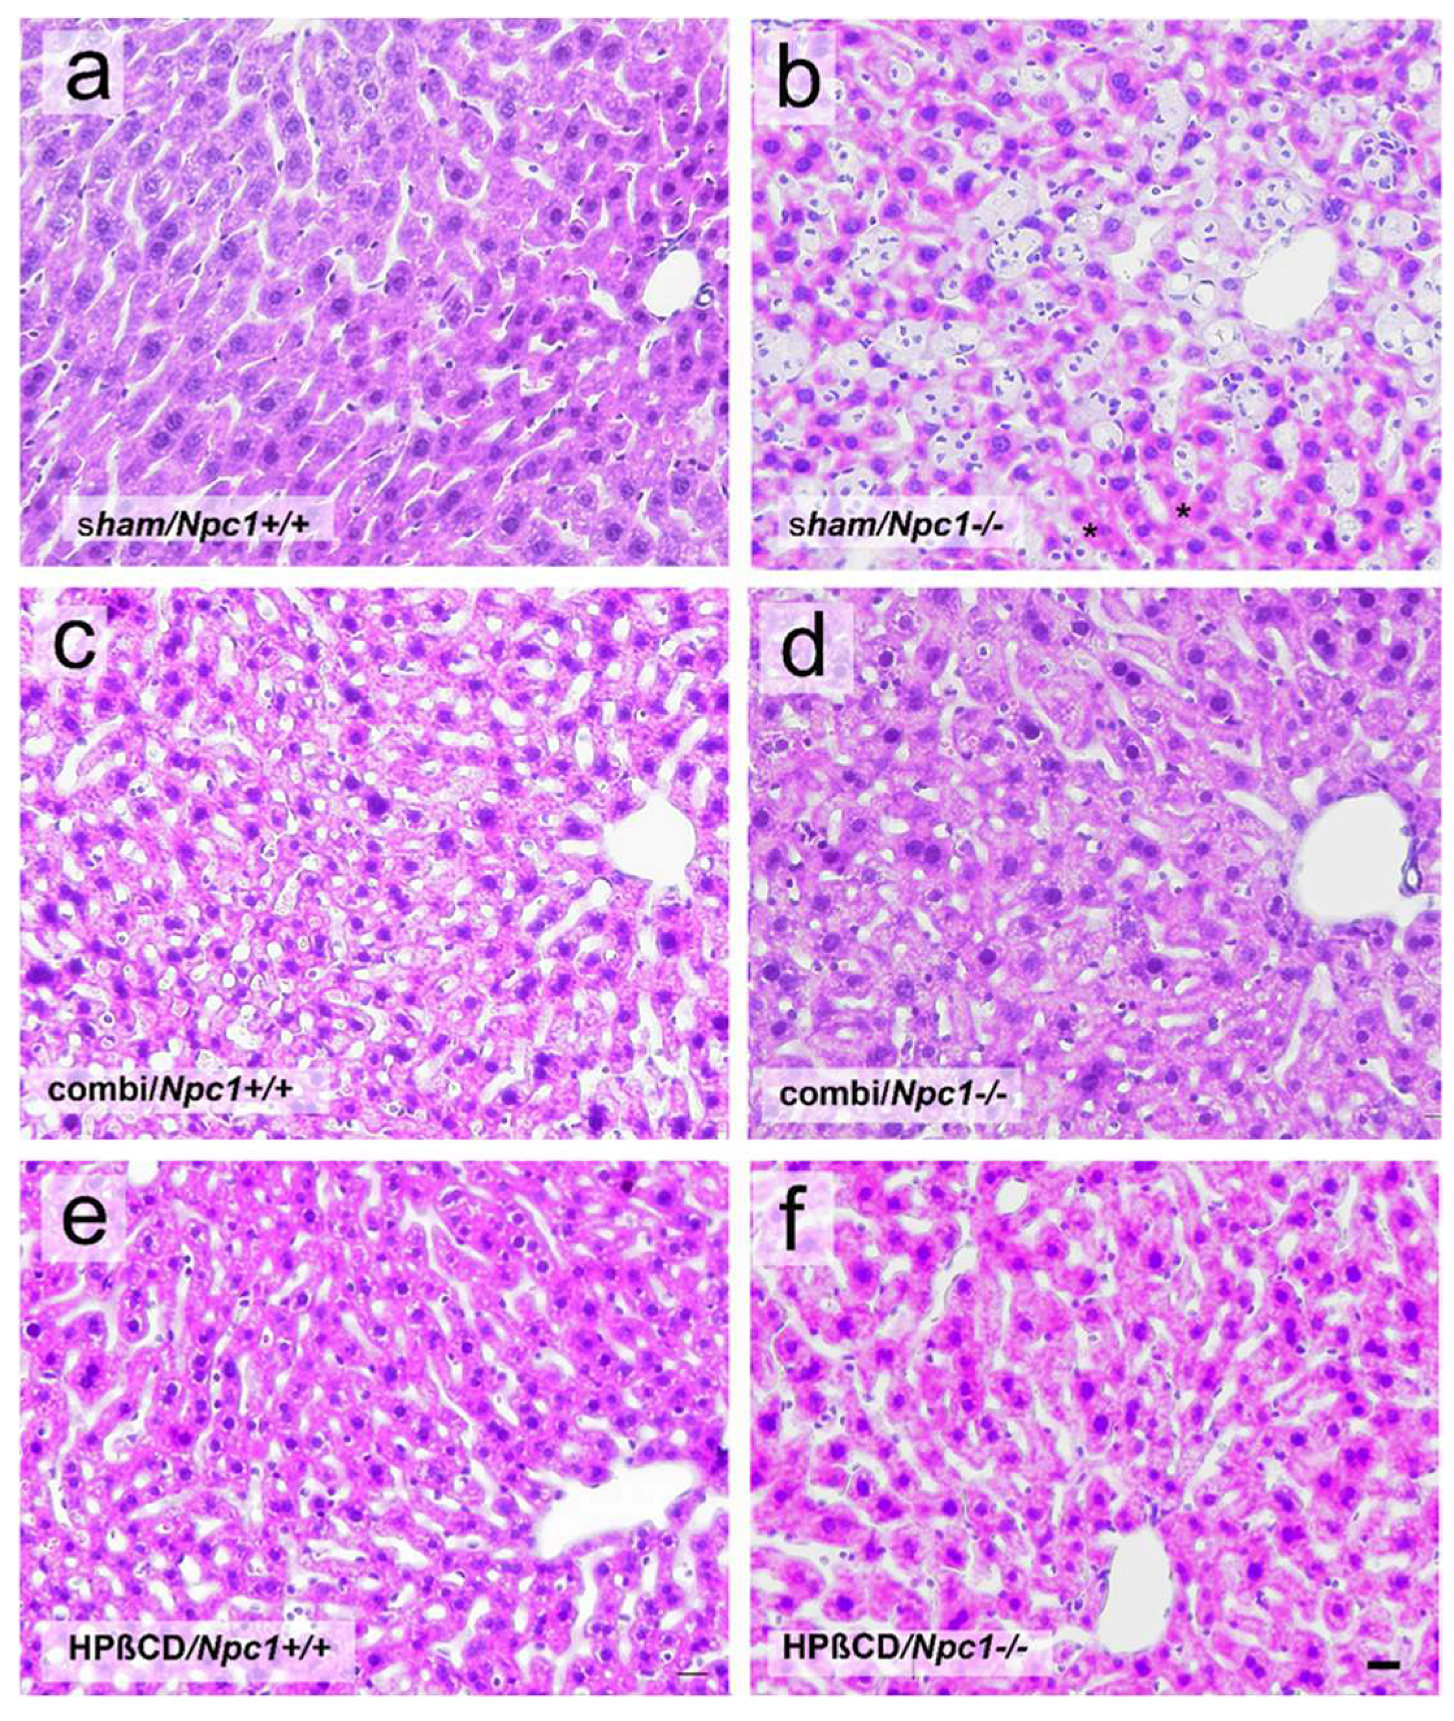

Болезнь Нимана-Пика Тип А: Симптомы и лечение

Раздел: Визуальный дайджест